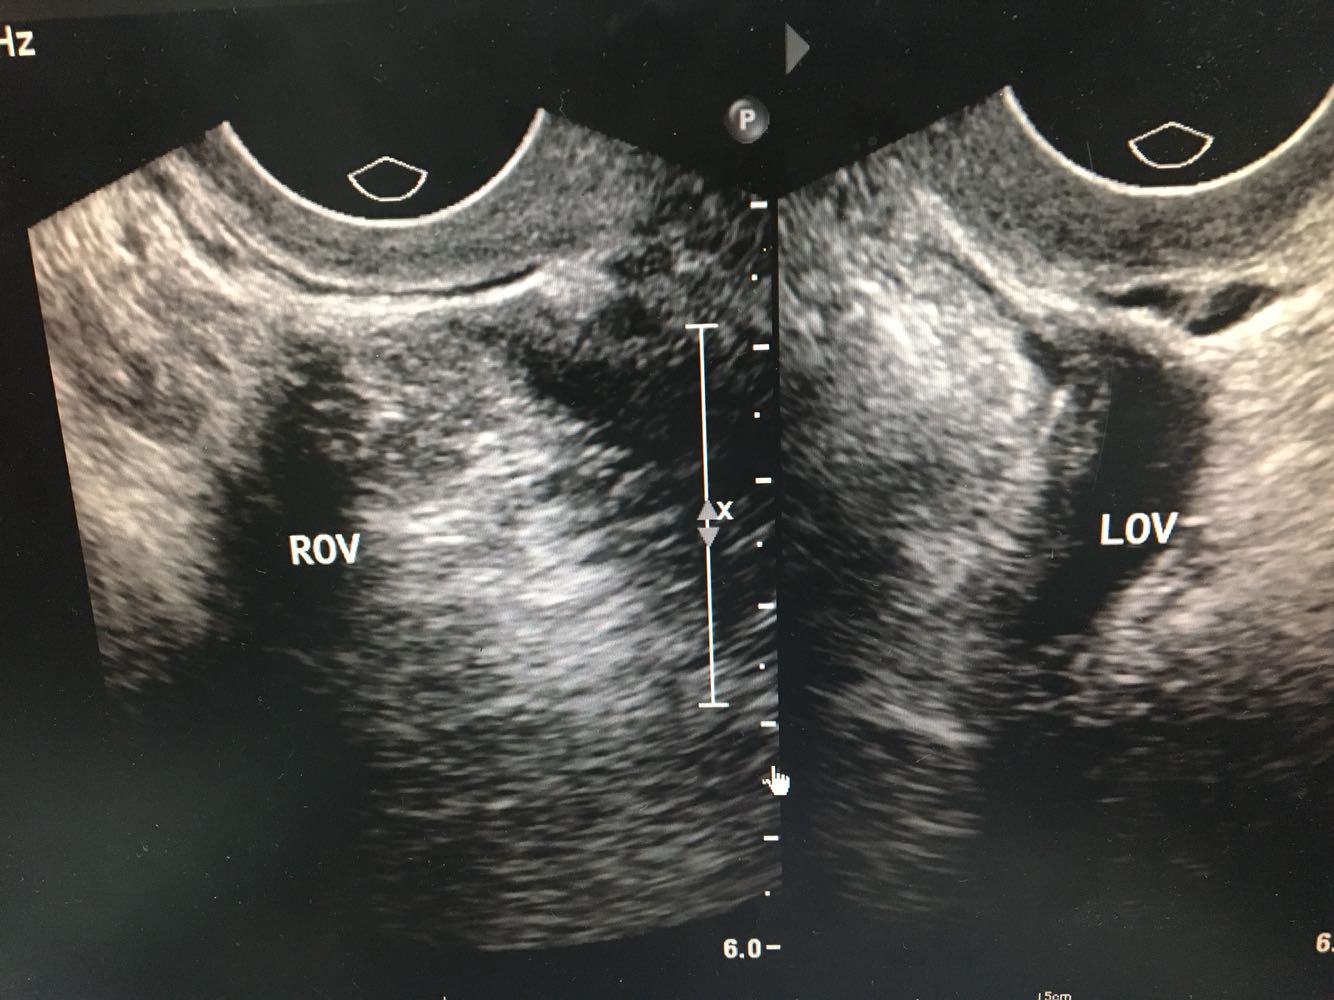

4、查体:外阴:(-)。阴道:通畅,阴道壁粘膜充血,散在出血点。子宫:屏气用力时可见子宫颈及阴道前壁脱出超过处女膜缘<1cm,子宫颈可见轻度柱状上皮外移,子宫体水平位,萎缩,活动良好,无压痛。附件:双侧附件未及明显包块及压痛。     5、辅检:【腹部B超】双肾囊肿;【妇科B超】子宫未见异常,双卵巢未探及